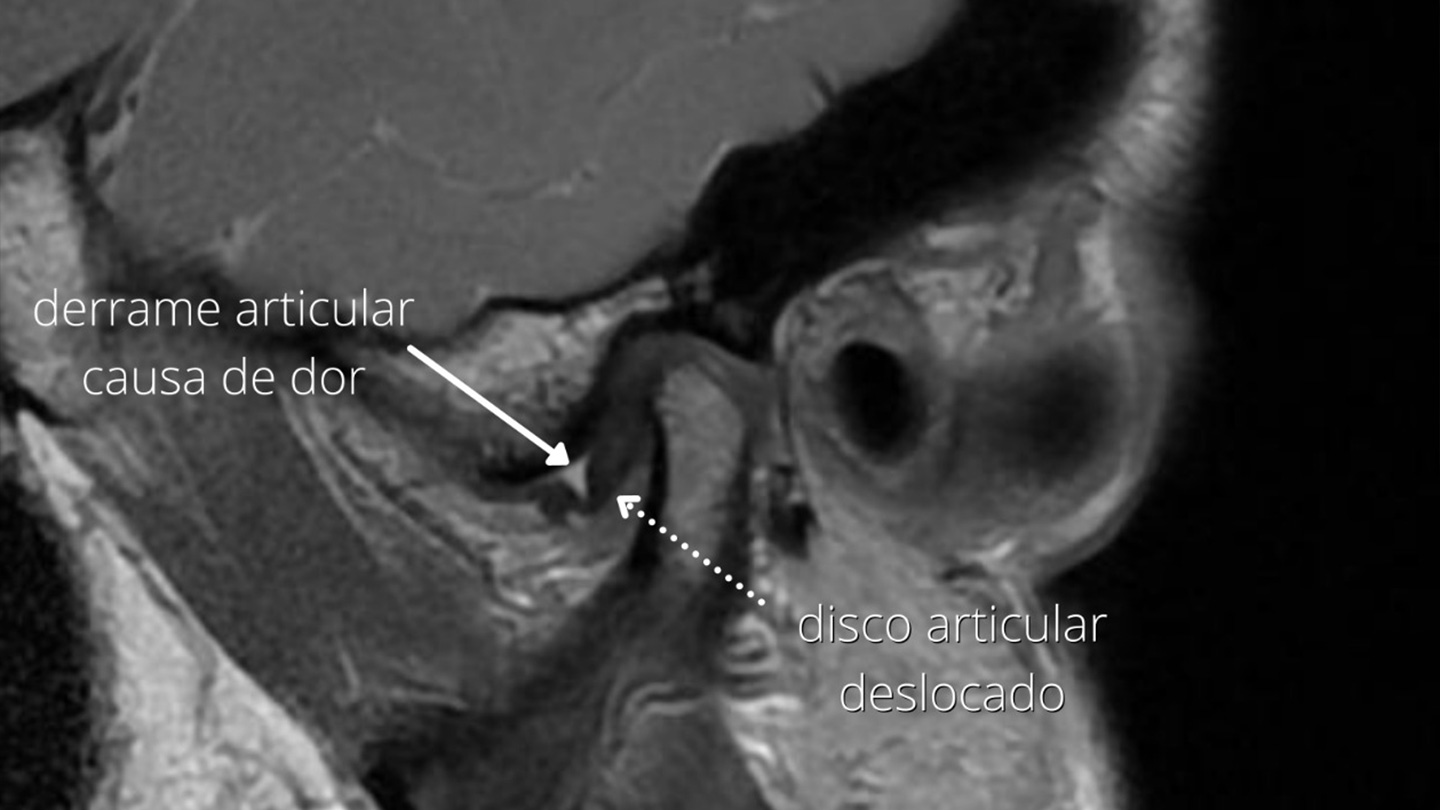

As alterações das articulações temporomandibulares podem causar transtornos da forma da face, do movimento da mandíbula e dor, referida na região lateral do crânio e da face. Podem estar presentes de forma isolada, ou associada com outras disfunções temporomandibulares, principalmente musculares.

Nos transtornos de dor recorrente ou crônica, o diagnóstico e compreensão da fisiologia da dor são essenciais para a correta indicação de tratamento clínico, farmacológico e funcional. A cirurgia tem papel secundário, contribuindo em casos selecionados. Nos quadros de dor, há uma cultura de tratamento mecânico, nem sempre eficiente, já que o fenômeno de sensibilização central – quando a origem da dor não está mais necessariamente conectada à lesão inicial que gerou o primeiro estímulo – associado a fatores psicológicos do paciente, tornam o tratamento mais complexo.

Pacientes com restrição prolongada da abertura da boca, com deformidades articulares ou com dor articular que não responda a métodos não invasivos podem ser candidatos à cirurgia. Principalmente nos transtornos que determinam dor ou limitação de movimento, as abordagens minimamente invasivas são desejáveis, por meio de procedimentos artroscópicos. As cirurgias abertas da articulação são indicadas como opção complementar, ou em casos onde a alteração da forma da articulação tenha repercussões funcionais ou mesmo na morfologia facial.